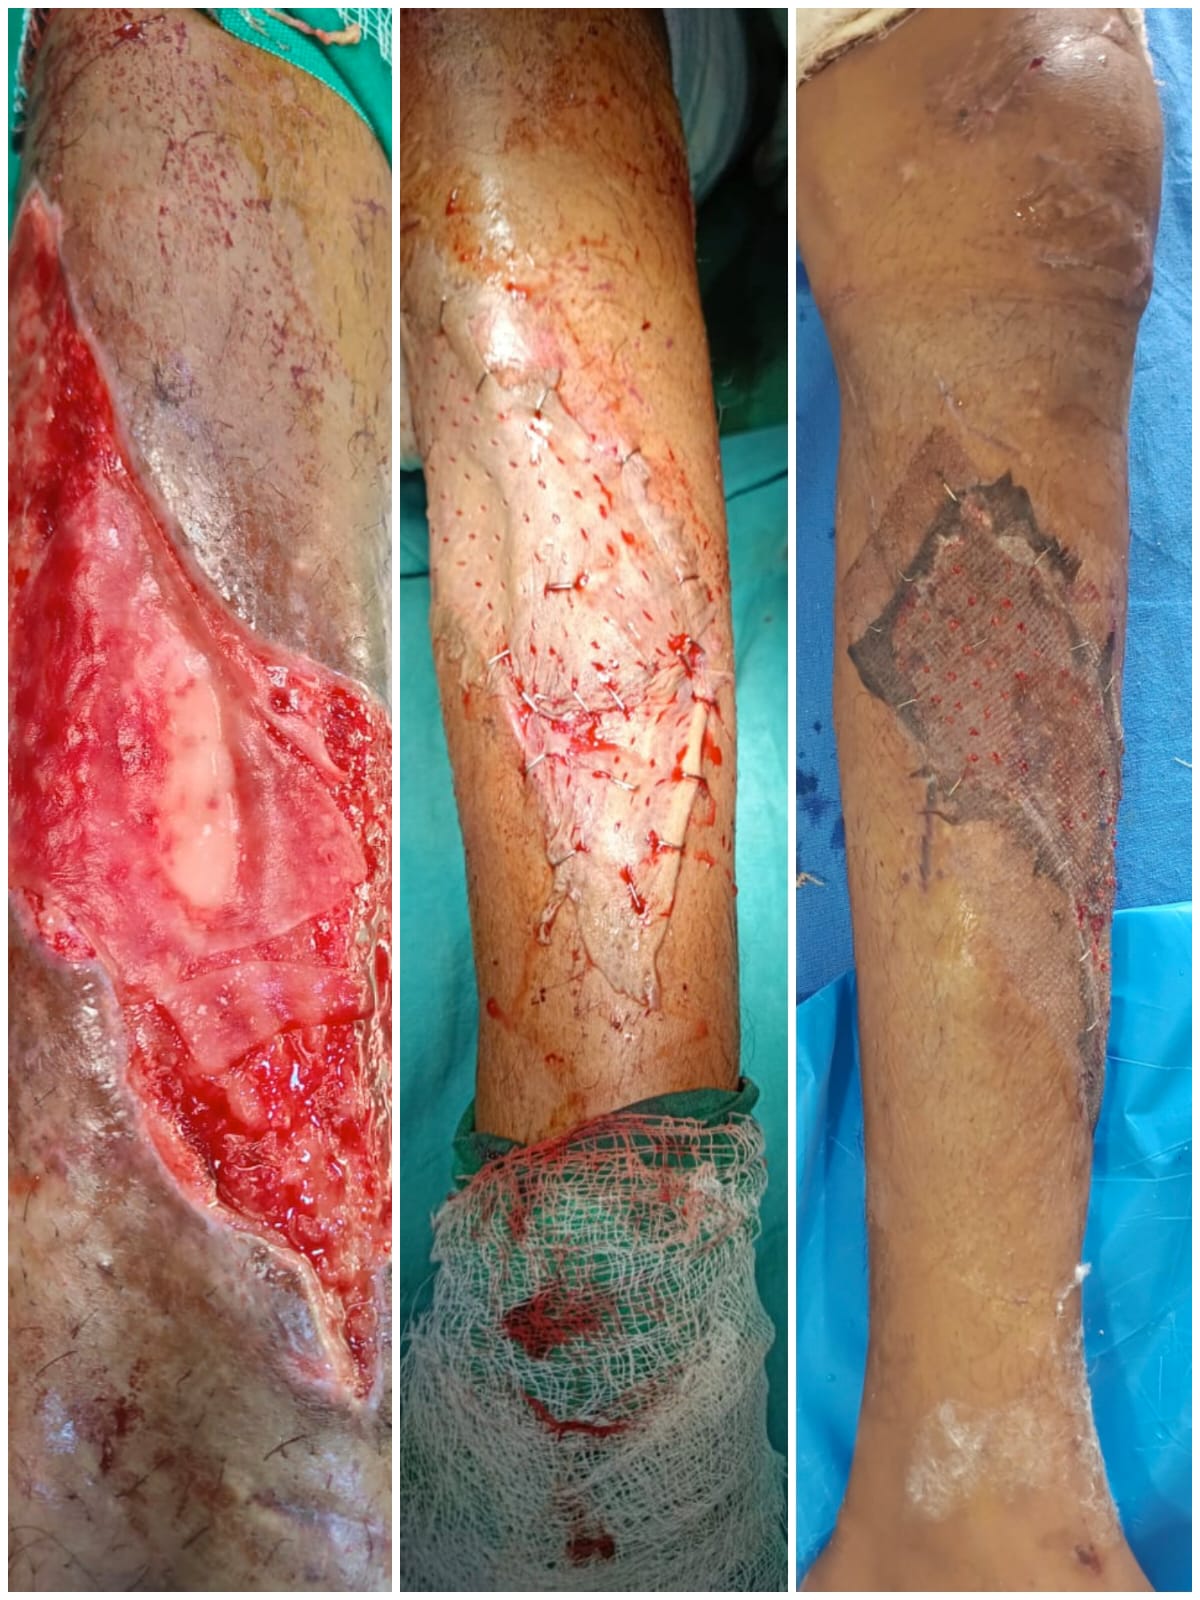

Welcome to our gallery, where you can explore a visual journey of our state-of-the-art surgical facilities, advanced medical equipment, and the exceptional care provided by our dedicated team. Here, you’ll find images showcasing our modern operating rooms, comfortable recovery areas, and the skilled professionals who ensure the highest standards of patient care.

Our gallery also features before-and-after photos of successful procedures, highlighting our commitment to transformative, evidence-based surgical practices. We invite you to browse through and witness the excellence and compassion that define our surgical practice.